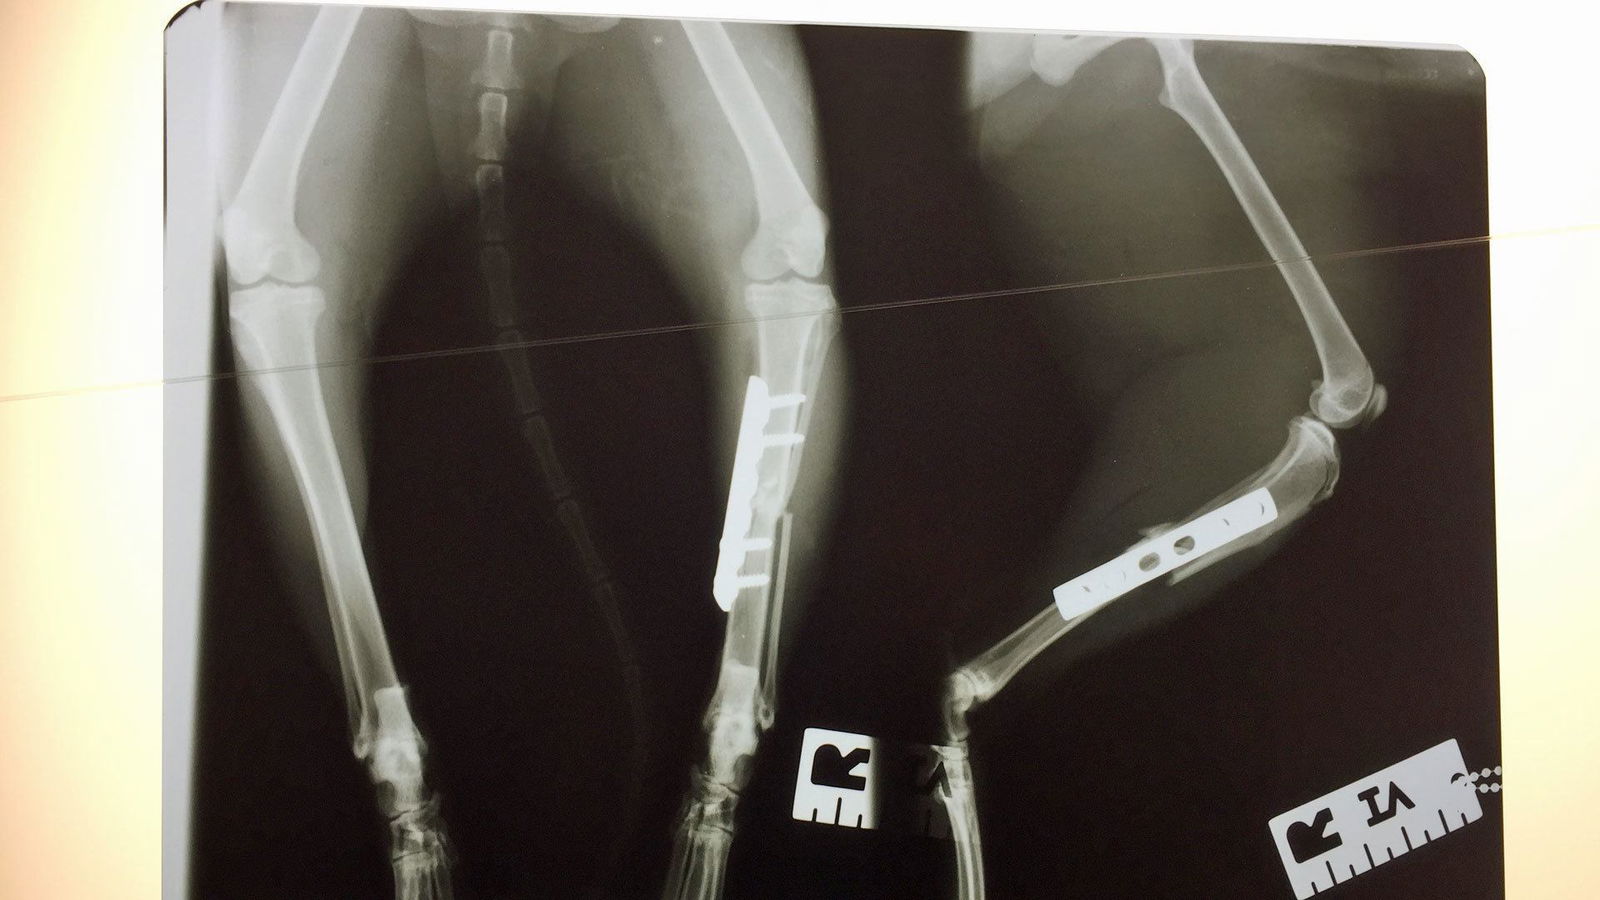

Super-Poschi und das Röntgenbild von Katze Jonsi